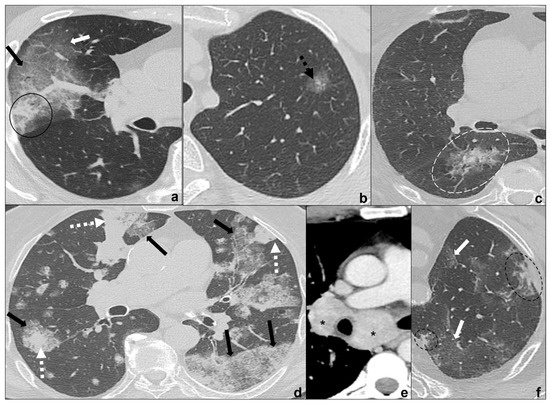

- generally focal entities, appearing as a single nodule (<3 cm) or mass (>3 cm) with invasive and infiltrative features;

- spiculated margins with pleural and parenchymal retraction stripes causing extensive pulmonary distortions and mediastinal attraction;

- inhomogeneous density in relation to hemorrhagic and/or necrotic foci (e.g., small cell carcinoma, large cell carcinoma);

- inhomogeneous contrast enhancement that is typical of cancer and is not seen in COVID-19 consolidations;

- possible endobronchial growth and spread through airspace (STAS), which has been recognized as a feature with prognostic significance in 2021 WHO classification of thoracic tumors;

- not generally associated with ground-glass or crazy paving areas. If ground-glass or crazy paving areas are present due to edema and hemorrhage, they do not follow COVID-19 pneumonia phases;

- may be central or peripheral, but do not present a strictly subpleural distribution (squamous cell carcinoma and small cell carcinoma being generally central tumors whilst large cell carcinoma being often peripheral);

- grow during antibiotics/anti-inflammatory therapies;

- cysts and/or cavitations (squamous cell carcinoma);

- chest wall, mediastinum and mediastinal organs invasion (frequent in small cell carcinoma, which is most common oncological cause of superior vena cava compressive/infiltrative/thrombotic obstruction);

- associated findings such as atelectasis (Figure 5d) and post-obstructive pneumonia (typical of endobronchial growing tumors such as squamous cell carcinoma;

- lymphangitis carcinomatosis;

- mediastinal lymphadenopathies and pleural effusions;

- systemic metastasis, which are particularly early and frequent in small cell carcinoma.